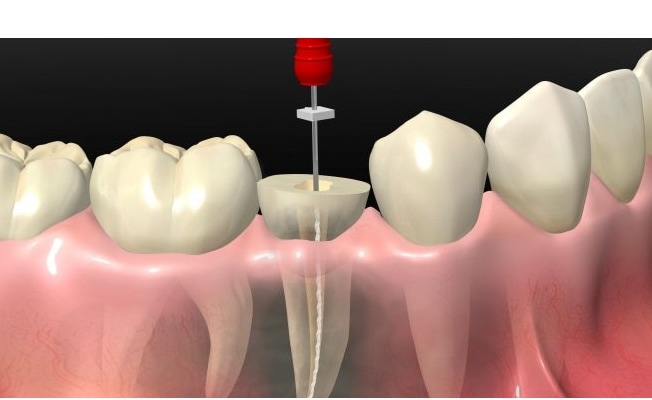

Kanal Tedavisi

Kanal Tedavisi

Dişe canlılığını veren Pulpa dokusunun ( kan damarları ve sinirlerden oluşan ) geri dönüşümsüz olarak enfekte olması sonucu dişin içerisindeki bu dokunun çıkartılması işlemidir. Genellikle bu dokunun enfeksiyonu ilerleyen çürük tabakasının dişin en alt tabakası olan pulpa dokusuna ulaşması sonucunda dişte soğuk ve sıcağa aşırı hassasiyet vermesi , gece zonklaması ve dayanılmaz ağrı şeklinde belirti vermektedir .

Diş çürükleri mine tabakasında başlayıp ardından bi alt tabaka olan dentin tabakasına ve son olarak pulpaya ulaşır ise bu durum artık geri dönüşümsüz olup kanal tedavisi kaçınılmazdır . Bu sebeble diş çürüklerinin erken tanısı dişin ömrü ve sağlığı açısından çok önemlidir .

Kanal tedavisi vital ( canlı ) ve devital ( cansız ) dişlerde tedavisi iki farklı şekilde yapılmaktadır . Canlı dişlerde tek seansta lokal anestezi işleminin ardından çürük dokusu temizlenerek , dişin enfekte olmuş pulpa dokusu ve kök kanalında bulunan kan damarı ve sinirler çıkartılır. Ardından bu kök kanalı sodyum hipoklörür ile bolca yıkanmasının ardından enfeksiyon kontrolü sağlanarak kurutulup kökö kanalları boşlık kalmayacak şekilde mühürlenir . Devital dişlerde ise belirti olarak enfekte bölgede apse ve ileri vakalarda sicvilce başı gibi fistül vermektedir.

Bu durumda kök kanalı yine vital dişlerde olduğu gibi yıkanıp temizlenmesinin ardından kalsiyum hidroksit gibi ilaçlarla geçici olarak kapatılır. Bu ilaçlar diş kökünün dışına taşmış lezyonlarda bakteri oluşumunu durdurucu etkiye sahiptir. İlgili bolgede enfeksiyon kontrolü sağlanana kadar hastalar haftalık olarak kontrollere çağırılarak her seansta kök kanalı içerisindeki antibakteriyel ajan değiştirilir . Enfeksiyon kontrolü sağlandıktan sonra yine kök kanalları mühürlenerek kapatılır .